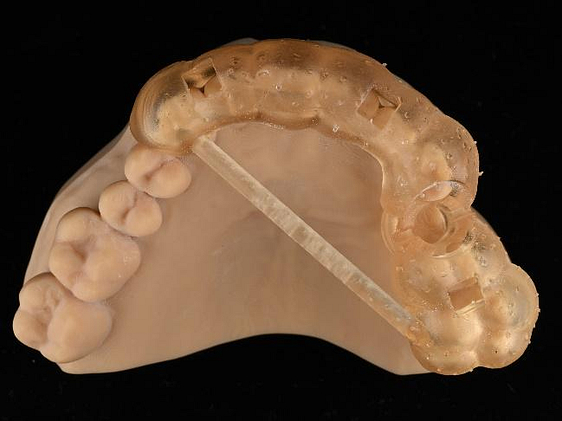

A custom surgical guide was designed and 3D printed, incorporating all the critical information from the virtual planning. The implant surgery was performed under local anesthesia, with the surgical guide firmly in place to ensure accurate implant placement. Bone grafting was performed to address the bony defect and promote optimal healing.

The Osstem OneGuide kit is used with a fully guided osteotomy and implant placement.